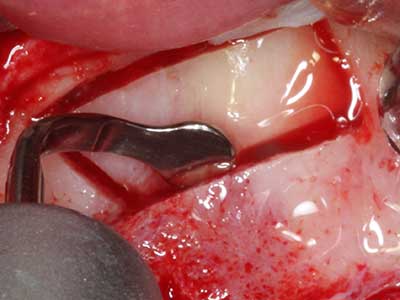

La piezochirurgia presenta altri vantaggi per quanto riguarda la raccolta di blocchi ossei. Oltre all'elevata precisione dell'osteotomia appena descritta, l'utilizzo di puntine per sega molto sottili permette di minimizzare in maniera significativa la perdita di materiale. È molto probabile che si verifichi una maggiore perdita di materiale durante la raccolta utilizzando puntine di strumenti più spessi, in particolare delle frese Lindemann (Lakshmiganthan, Gokulanathan et al. 2012). La separazione basale, necessaria in particolare per i trapianti di blocchi nella zona retromolare, viene semplificata grazie a seghe specificatamente progettate di forma rettangolare; di conseguenza la piezochirurgia è considerata una procedura precisa, semplice e sicura per la raccolta di blocchi di osso nella zona retromolare (Happe 2007) (figg. 1-12).